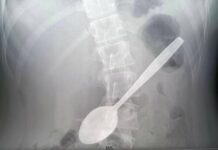

Несмотря на лечение, улучшений не последовало. Ребенка госпитализировали в больницу имени Башляевой, где команда специалистов предположила, что причина недомогания кроется в другом. Рентген и бронхоскопия подтвердили догадку: в дыхательных путях находился кусочек курицы размером 4×1 см, блокирующий доступ кислорода. После его удаления здоровье мальчика стремительно пошло на поправку!

— Даже современные методы диагностики, такие как рентген, не всегда помогают сразу обнаружить проблему, — отметили врачи. — Точный сбор данных и внимательность специалистов позволяют быстро выявить инородный объект и провести необходимое вмешательство.